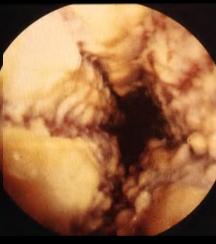

Image macroscopie endoscopique de

candidose oesophagien |